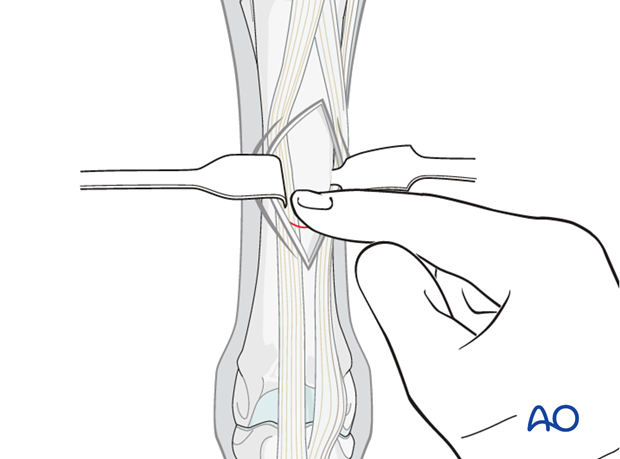

The incision is made directly down to the bone usually splitting the common digital extensor tendon from the lateral or simply splitting the edge of the combined tendon. If it is a more lateral fracture, the incision is made completely lateral to the tendons.

The incision is approximately 4 cm in length and should go all the way down to the bone.

The scalpel can be turned over and the end of the handle used as a periosteal elevator. Alternatively the surgeon can use a standard elevator to expose the surface of the bone.

The actual fracture can only rarely be seen. Usually the surgeon can palpate the small callus on the surface of the bone.

Spreading of the edges of the incision with a sharp Weitlaner retractor is useful.